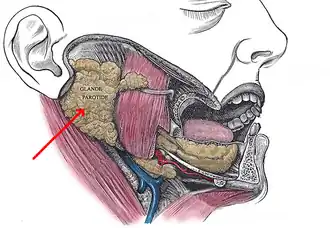

La glande parotide est située entre la branche montante de la mandibule en avant, le conduit auditif externe au-dessus, et la mastoïde en arrière. Elle est comprise dans une capsule fibreuse, et contenue dans une loge, appelée loge parotidienne.

Chez l'homme, la glande parotide est la plus volumineuse des glandes salivaires principales, pesant 25 à 30 grammes chez l'adulte. De forme pyramidale, à sommet médial et base latérale, elle est moulée sur les parois de la loge parotidienne, entre la région rétro-stylienne en arrière, la région parapharyngée en dedans et la fosse infra-temporale en avant.

Elle est traversée par le nerf facial (qui dérive de la septième paire de nerf crânien, responsable de la mimique). C'est le principal élément nerveux, qui forme par ses ramifications terminales le plexus parotidien et qui divise la glande en deux lobes : superficiel et profond. Il y chemine également le nerf auriculo-temporal, branche du nerf mandibulaire.

La loge parotidienne a une forme de prisme à sommet médial et base latérale dans laquelle va venir se mouler la parotide. Elle est limitée en postérieur par le diaphragme stylien, dans sa portion située en dehors du ligament stylo-hyoïdien. La paroi antérieure est formée de dehors en dedans par le muscle masséter, la branche de la mandibule, le ligament sphéno-mandibulaire, le muscle ptérygoïdien médial puis par le ligament stylo-mandibulaire. L’extrémité supérieure de cette région est étroite, formée par le méat acoustique externe en arrière et l’articulation temporo-mandibulaire en avant. Son extrémité inférieure est large, et correspond à la cloison inter-mandibulo-parotidienne elle-même formée de la bandelette mandibulaire en dehors, qui unit l’angle mandibulaire au muscle sterno-cléido-mastoïdien, et du ligament stylo-mandibulaire en dedans. Cette cloison est traversée par les veines jugulaire externe et rétro-mandibulaire et marque la limite avec la région submandibulaire.

La glande parotide peut présenter plusieurs prolongements anatomiques. En avant, il peut exister un prolongement dans le tunnel stylo-mandibulaire, aussi dénommé boutonnière rétro condylienne de Juvara, situé en dedans du col du condyle. Ce trajet est aussi emprunté par le paquet vasculo-nerveux maxillaire et le nerf auriculo-temporal. En dehors elle présente deux prolongements souvent volumineux : un prolongement antéro externe en dehors de la face latérale du muscle masséter, et un prolongement postéro-externe qui déborde sur la face latérale du muscle sterno-cléido-mastoïdien. En arrière, on peut retrouver un prolongement traversant le rideau stylien, entre le muscle stylo-hyoïdien et le ventre postérieur du muscle digastrique. En dedans, la glande peut aussi se prolonger entre le ligament sphéno-mandibulaire et le ligament sphéno-maxillaire, pour donner un prolongement qui se développe alors aux dépens de l’espace para-pharyngé.

Éléments anatomiques traversant la parotide

La parotide est traversée par différents éléments vasculo-nerveux, avec de dedans en dehors :

- le nerf auriculo-temporal ;

- l’artère carotide externe ;

- le plexus veineux intra- parotidien ;

- puis le nerf facial, qui délimite artificiellement la parotide en deux lobes : superficiel en dehors et profond en dedans.